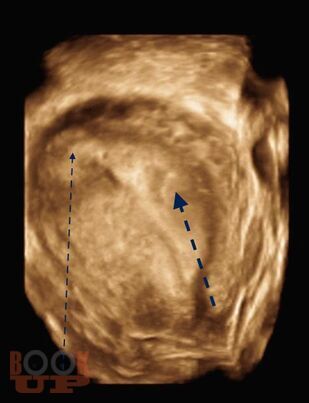

Интерстициальная и угловая (ангулярная) беременность

В учебно-методическом пособии приведен сравнительный анализ существующих методов лечения беременности в интерстициальном отделе маточной трубы и ангулярной беременности. Подробно изложен собственный запатентованный протокол лечения интерстициальной трубной беременности в зависимости от данных ультразвукового исследования в совокупности с уровнем ХГЧ в сыворотке крови беременной, разработанный авторами. Данный протокол позволяет на основании полученных диагностических данных выбрать оптимальный метод органосохраняющего лечения, определить методы последующего контроля состояния пациента.